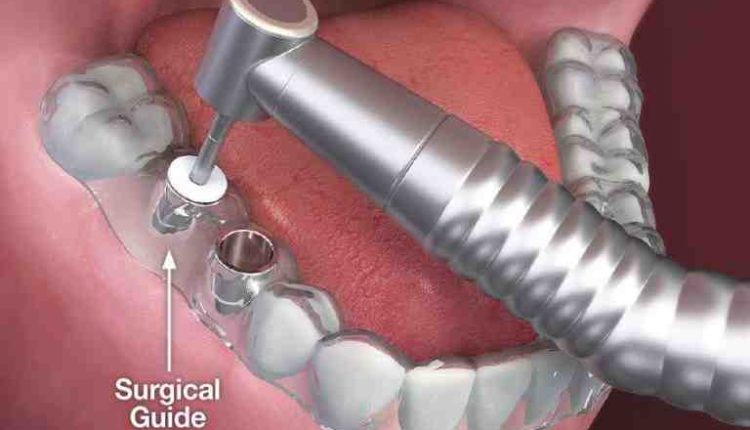

How long do teeth implants take?

Implant Surgery Your dentist will place a titanium implant in your jawbone, just under the gums. This operation usually takes 1-2 hours for each implant to be placed. After this step is completed, most dentists will wait around 3 months before the final restoration of the tooth replacement.